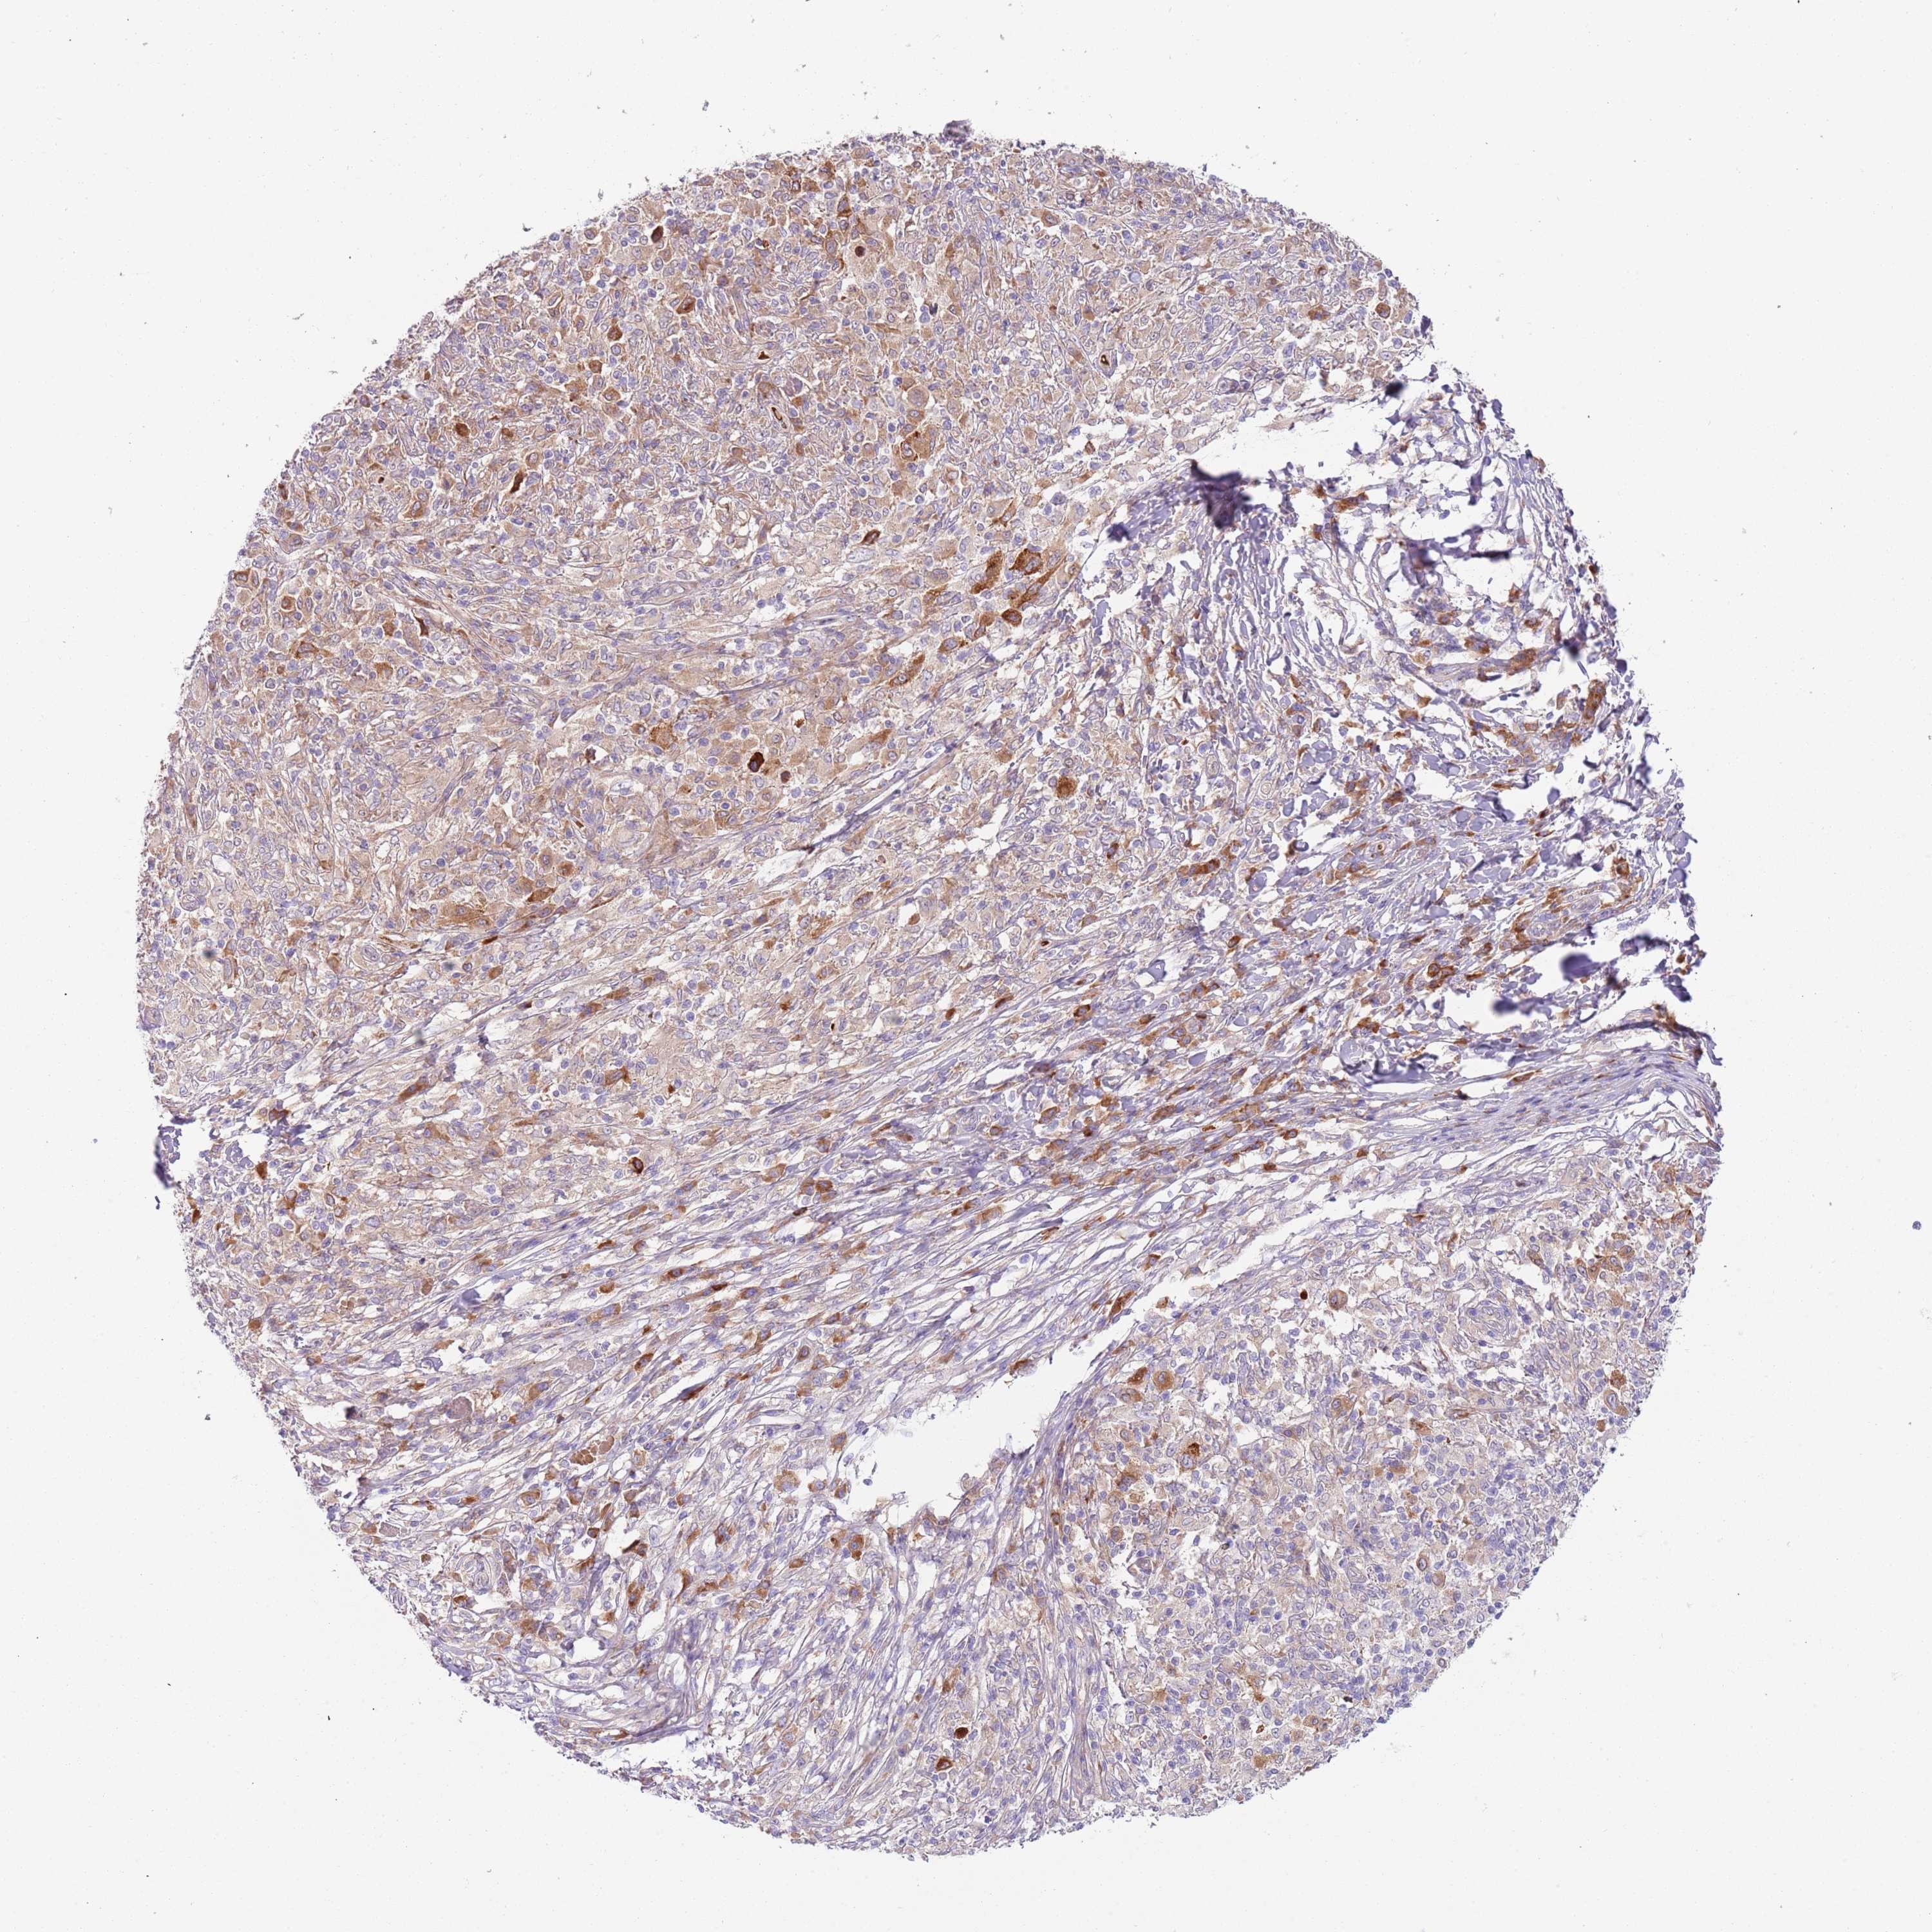

MELANOMA - Protein expressioni

A mouse-over function shows sample information and annotation data. Click on an image to view it in a full screen mode. Samples can be filtered based on level of antibody staining by selecting one or several of the following categories: high, medium, low and not detected. The assay and annotation is described here.

Note that samples used for immunohistochemistry by the Human Protein Atlas do not correspond to samples in the TCGA dataset.

Antibody stainingi

Antibody staining in the annotated cell types in the current human tissue is reported as not detected, low, medium, or high, based on conventional immunohistochemistry profiling in selected tissues. This score is based on the combination of the staining intensity and fraction of stained cells.

Each image is clickable and will lead to virtual microscopy that enables deeper exploration of all samples and also displays staining intensity scores, fraction scores and subcellular localization as well as patient and tissue information for each sample.

Antibody HPA040401

Antibody HPA043921

Staining

High

Medium

Low

Not detected

Intensity

Strong

Moderate

Weak

Negative

Quantity

>75%

75%-25%

<25%

None

Location

Nuclear

Cytoplasmic/membranous

Cytoplasmic/membranous,nuclear

Malignant melanoma, NOS

Malignant melanoma, Metastatic site